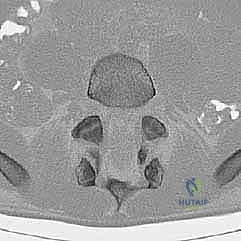

التصوير المقطعي المحوسب (CT Scan):

يوفر تفاصيل دقيقة للغاية عن البنية العظمية. يُستخدم بشكل خاص لتقييم العيوب العظمية بدقة (مثل كسر البرزخ المفصلي)، وللتخطيط الجراحي الدقيق قبل إجراء عملية التثبيت.